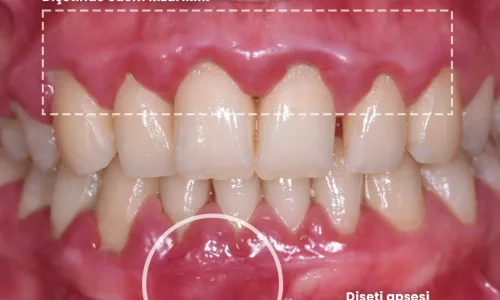

Gum Disease, Bleeding Gums and How to Save Your Teeth

Gum disease, bleeding gums, and how to save your teeth. Learn the symptoms of gingivitis and advanced periodontitis, discover effective treatment methods, and understand the steps you must take to prevent tooth loss.